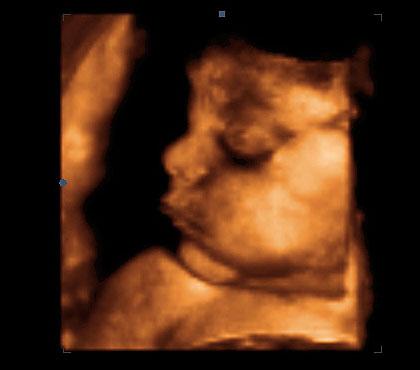

Ve 28. týdnu těhotenství měří plod zhruba 38 cm. Pro určení délky plodu se nyní používá součet délky hlavičky, trupu a nohou. Váha plodu je nyní zhruba 1000 g.

Plod má již pěkně formované všechny části obličeje. Oddělení očních víček dokumentuje jasně patrný okraj horního víčka, které má také již dobře vyvinuté řasy.